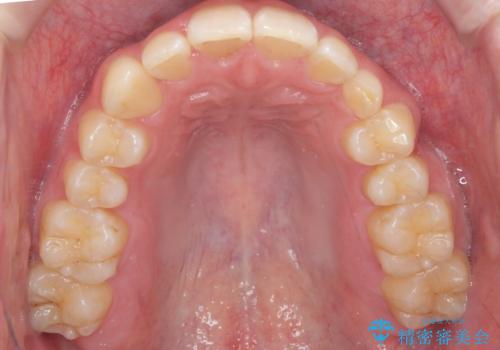

将来的にインプラントは希望されないとのことだったため、乳歯の部分は隙間を開けてインプラントを入れる用のすき間を確保するということは特に行いませんでした。

乳歯をそのまま並べたため、上顎の左右の犬歯の幅は非対称になっています。